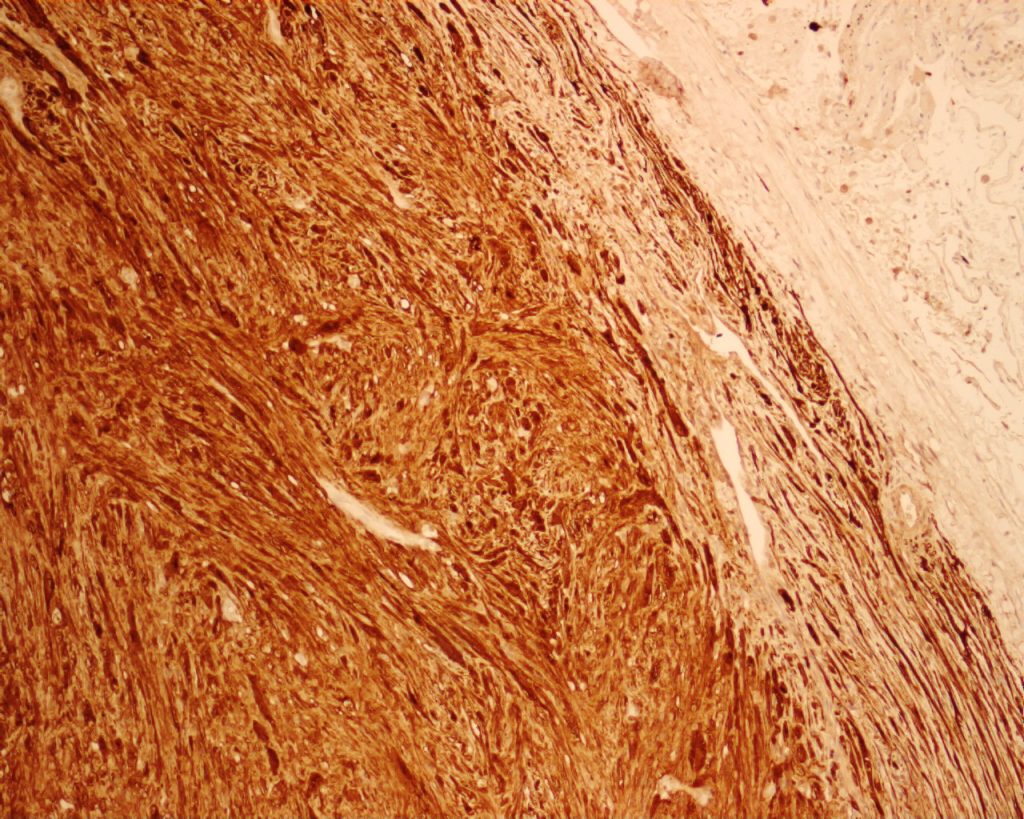

She was seen by cardiothoracic surgeon one year later, flexible bronchoscopy was repeated on 31 May 2011, it showed a roundish cystic mass obstructing LB6. Bronchial biopsy showed endobronchial schwannoma.(fig 3&4). Lt. thoracotomy with left lower lobectomy was done on 25 July 2011. Pathology showed endobronchial schwannoma with clear margins.

Fig. 4 (Above) Strong diffuse staining for S100

protein confirmed the diagnosis of schwannoma